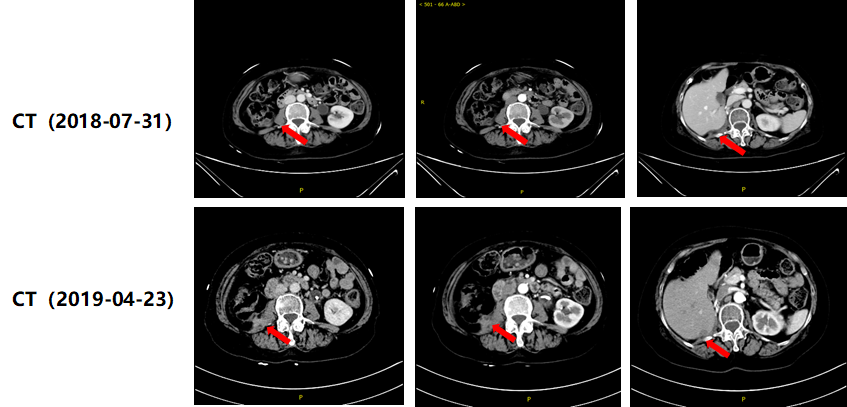

2017年9月,患者因“间断无痛性肉眼血尿两周余”首次就诊,9月14日腹盆腔CT平扫示:右肾形态饱满,右侧肾盂及输尿管上段多发囊性灶,局部囊壁增厚,伴周围多发渗出(图1)。10月10日腹盆腔增强CT示:右侧肾盂及输尿管中上段病灶;考虑右侧输尿管中上段Ca伴右侧肾盂及输尿管积水(图1)。

image001.png

图1.患者手术前CT影像资料